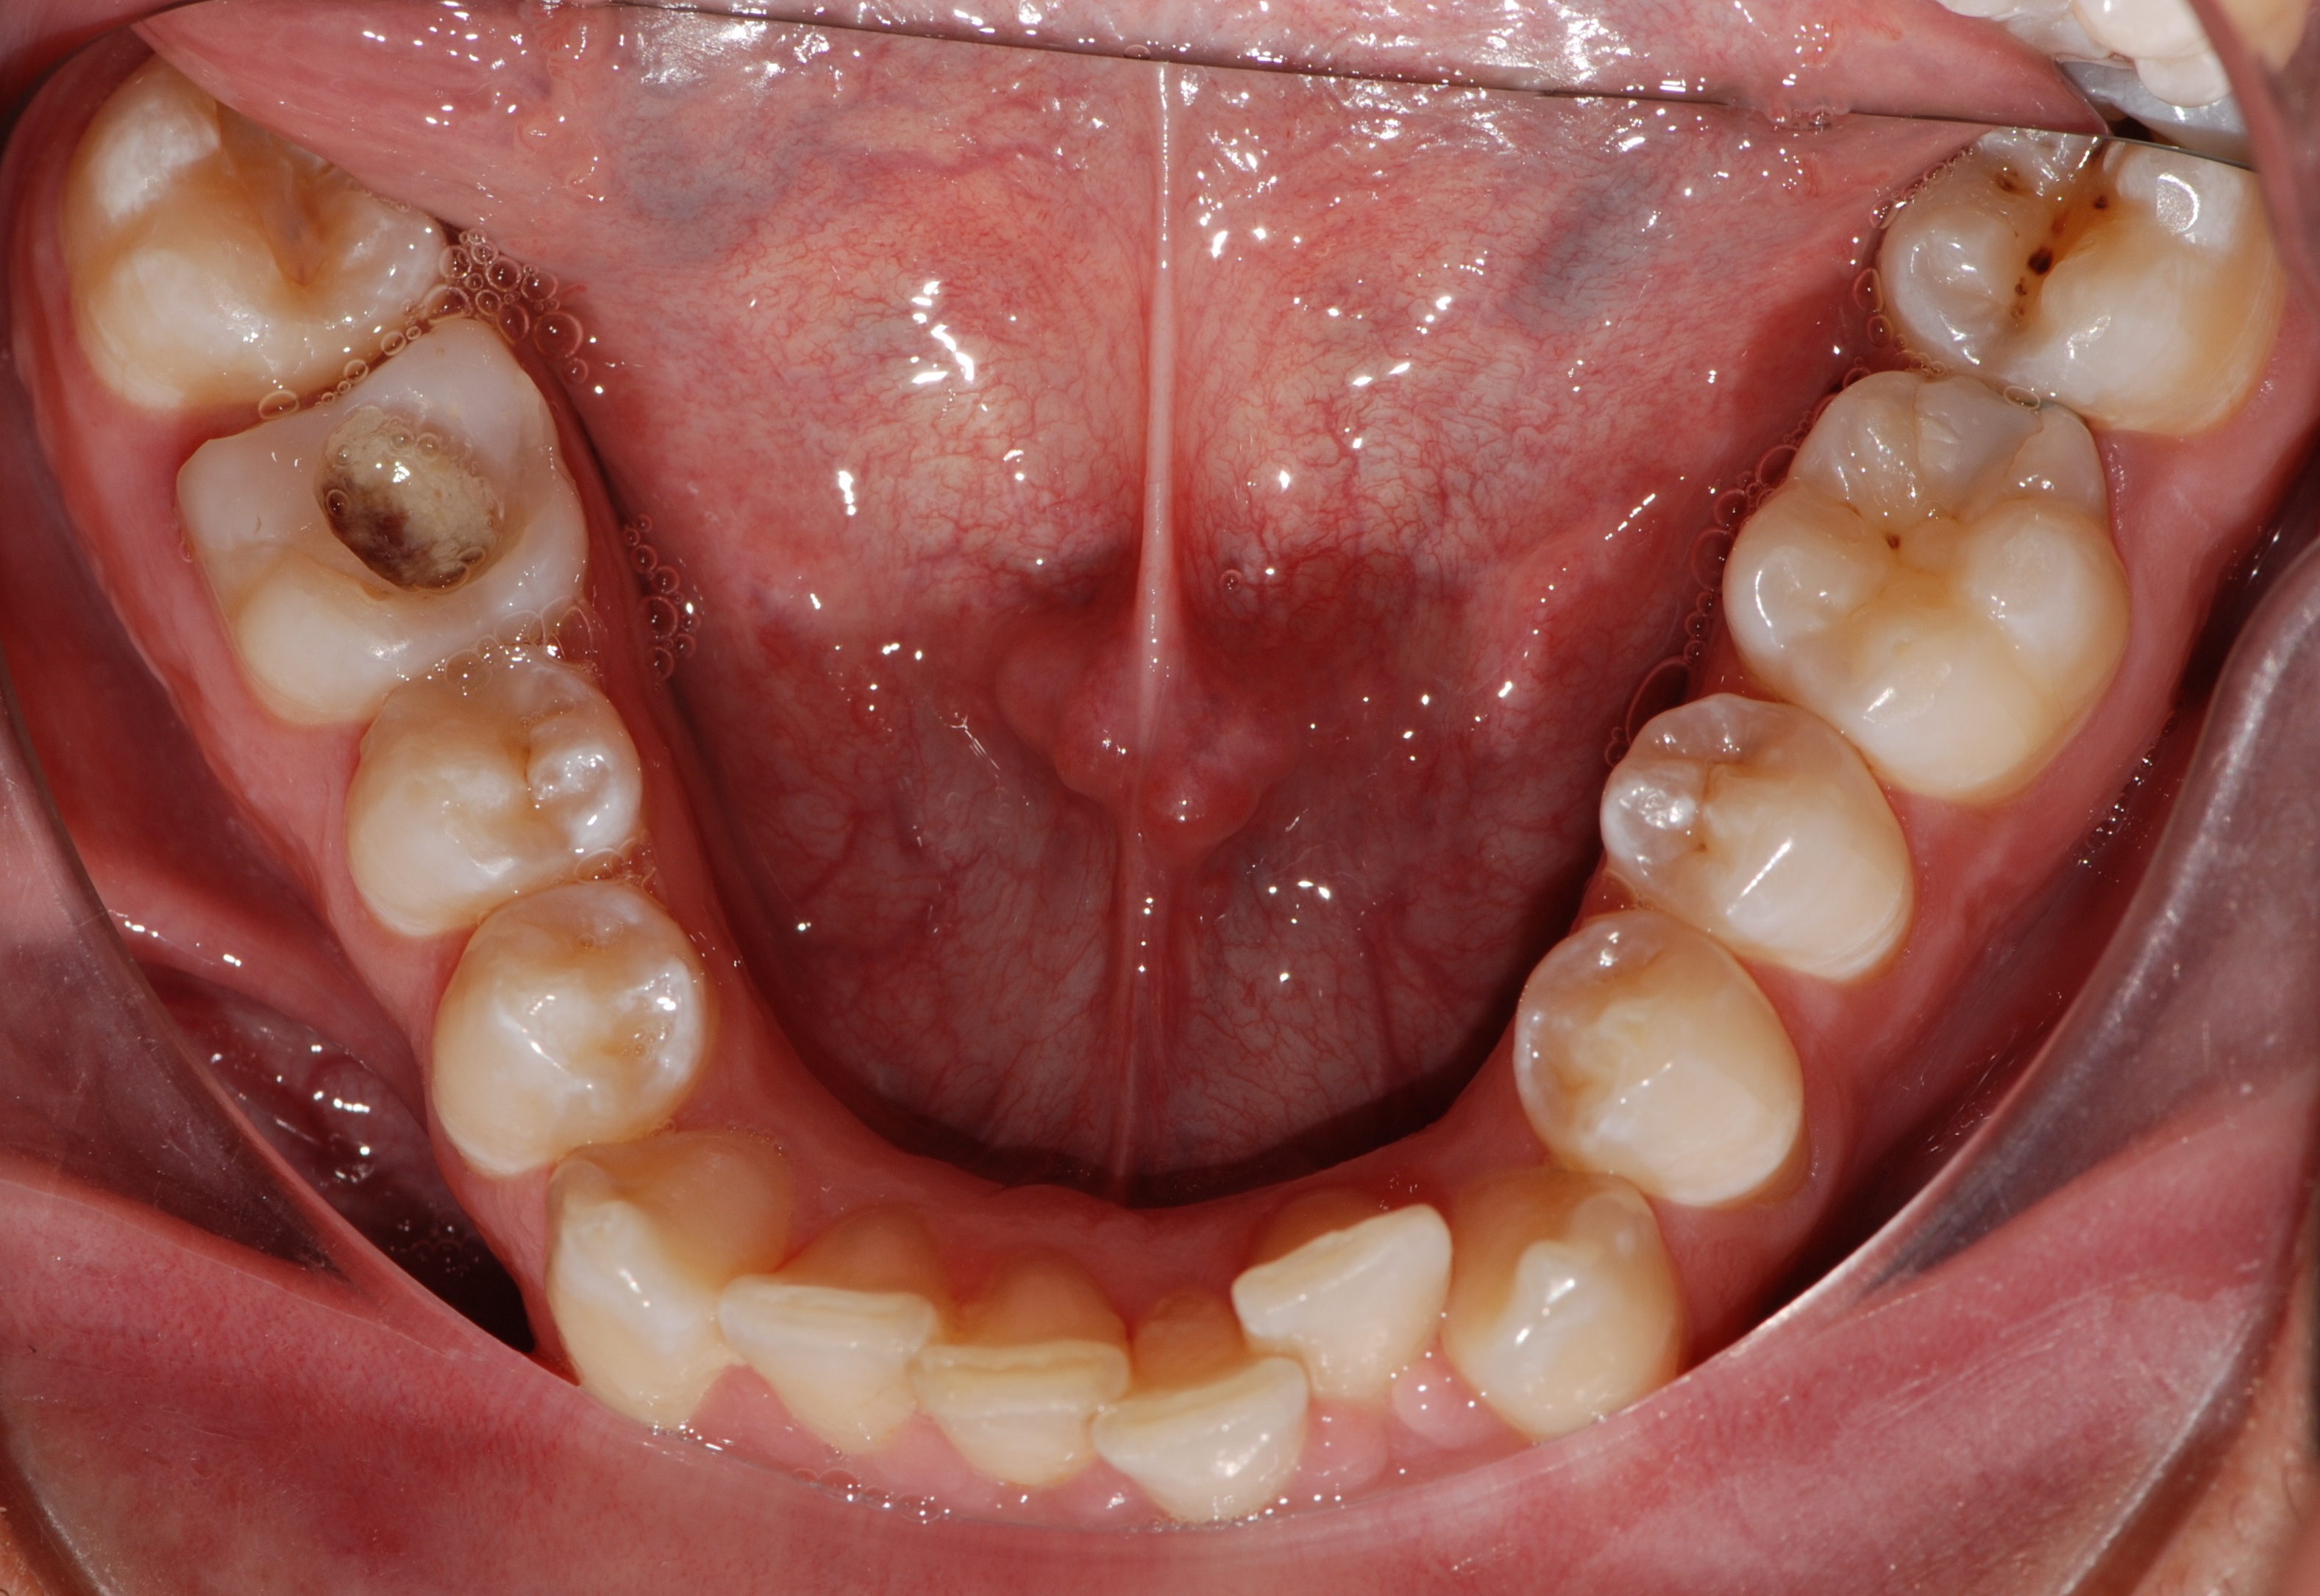

Paziente di 30 anni - Espansione dento-alveolare delle arcate e correzione affollamento grave con Invisalign; 48 mascherine; 2 anni di trattamento.

Giuseppe A. 30 anni

inizio trattamento